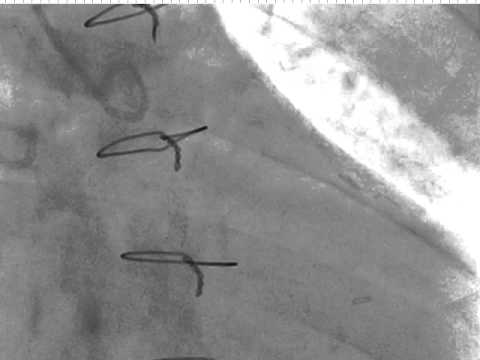

Video 7.5

Video 7.5: Engaging the RCA with the MP catheter